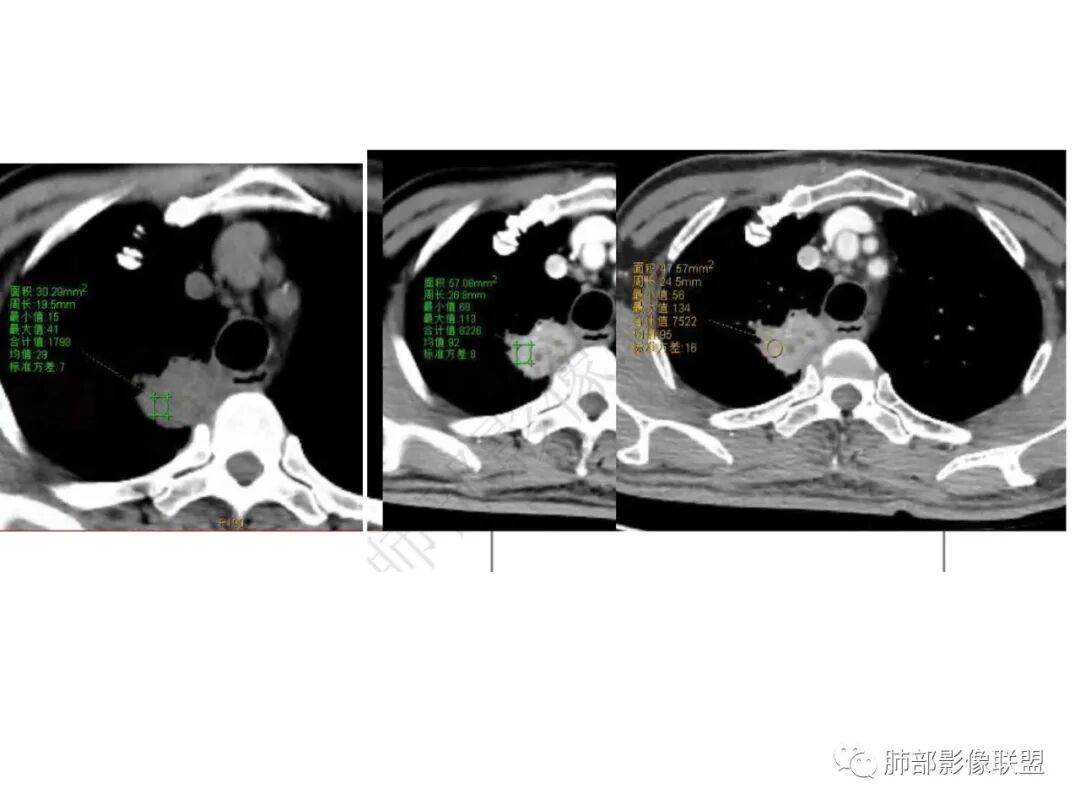

红日初升:老年男性,干咳十天,无发热,血象、肿标不高。右肺上叶团片,叶段分布,边缘多平直凹陷,强化见三层结构,考虑脓肿。边缘局部膨隆,近侧支气管阻塞,恶性不能排除,建议治疗后复查

丽:老年男性,急性病程,右肺上叶团片状高密度影,边缘有膨隆也有平直,胸膜下脂肪间隙消失,增强后明显强化,静脉期持续强化,并见条形低密度影无强化,考虑慢性炎症,建议抗炎治疗后复查除外恶性

爱跳舞的猫:老年男性,干咳,无发热,血象、肿标不高。右肺上叶团片影,呈条状,边缘多平直,增强扫描明显强化,其内见无强化坏死区,内壁光滑,考虑脓肿,建议治疗后复查除外恶性

信人生:老年男性,急性病程,右肺上叶尖后段团片状高密度影,明显桃尖征象,胸膜下脂肪间隙消失,增强后明显强化强化值约60HU,静脉期持续强化,并见条形低密度粘液栓,化验肿标及结核抗体均阴性,白细胞不高,考虑炎性肉芽肿/慢性炎症,建议抗炎治疗

实变区强化较均匀,明显强化

边缘平直为主